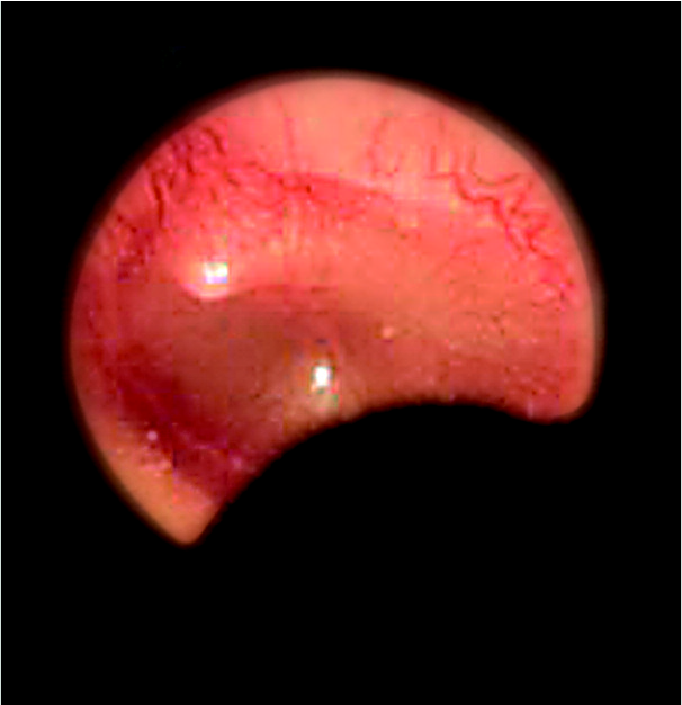

Ωτοσκόπιο Οπτικής Ίνας Heine K®180 Κεφαλή Ωτοσκοπίου ψυχρού φωτισμού από πολυκαρβονικά υλικά για γενική χρήση. Διαθέτει μεγάλο παράθυρο παρατήρησης & Θύρα πνευματοσκόπισης. Το παράθυρο περιστρέφεται και κλείνει αεροστεγώς. Περιφερειακός φωτισµός Οπτικής Ίνας µε τεχνολογία Αλογόνου (Xenon) XHL. Ομοιογενής, χωρίς αντανακλάσεις φωτισµός καναλιού ακοής και τυµπάνου. Μεγάλο παράθυρο παρατήρησης , μεγέθυνσης 3x. Ανεμπόδιστη εικόνα, χωρίς παραμορφώσεις. Αεροστεγές παράθυρο. Αξιόπιστη εξέταση πνευματοσκόπισης. Το παράθυρο περιστρέφεται και είναι βιδωμένο στην κεφαλή. Εύκολη χρήση και άλλων εργαλείων, δεν χάνεται. Από ανθεκτικά πολυκαρβονικά υλικά και ακρυλικό παράθυρο παρατήρησης που δεν χαράζεται. Το προιόν δεν συνοδεύεται από πηγή τροφοδοσίας (λαβή μπαταριών ή επίτοιχη τροφοδοσία).Για πλήρη λειτουργικότητα και απόδοση φωτισμού συνδυάστε το Ωτοσκόπιο Heine K®180 με λαβή επαναφορτιζόμενων μπαταριών ή επίτοιχη μονάδα τροφοδοσίας.